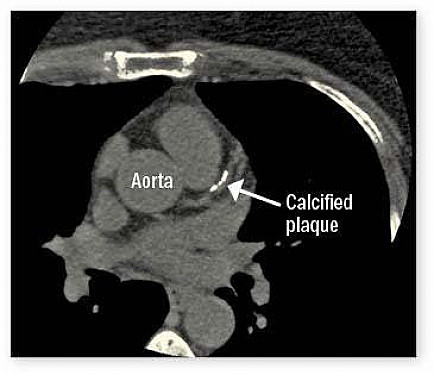

When your doctor orders an occasional x-ray or computed tomography (CT) scan, you probably focus on the findings, not the amount of radiation you'll be exposed to. But if you need numerous tests, you may wonder if you're getting too much radiation exposure and how it might affect you. The concern about radiation exposure is an increased risk for developing cancer later in life. Ionizing radiation from tests such as x-rays or CT scans has the potential to damage tissue in the body, including cell DNA.